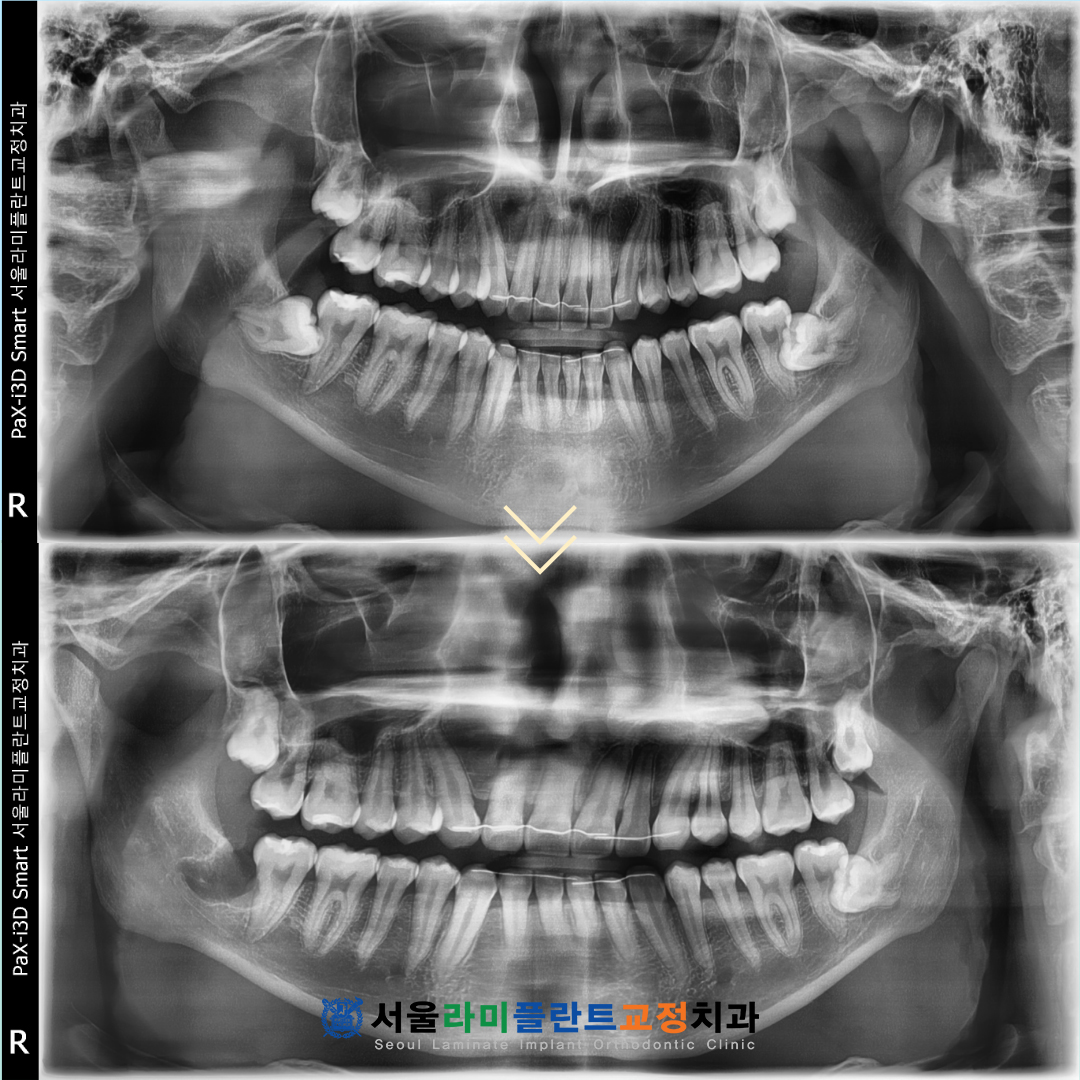

26.02.21

그 결과 하치조신경관에

매우 밀접해 있던 사랑니였음에도 불구하고

어떠한 신경 손상이나 합병증 없이

발치가 성공적으로 이루어졌습니다.

우려했던 치근 파절이나 뿌리 조각이

남는 문제 없이 치아 전체가 깨끗하게 발치되었으며

환자분께서 걱정하셨던 감각 이상 증상

또한 전혀 나타나지 않았습니다.

환자분께서는 다른 치과에서

어렵다고 했던 케이스를

통증이나 부작용 없이

깔끔하게 끝났다는 점에 대해

매우 높은 만족감을 표현해 주셨습니다.